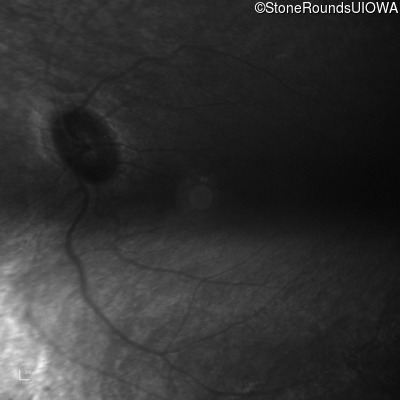

Infrared Fundus Photograph - Right - 20/100 +1

Exemplar